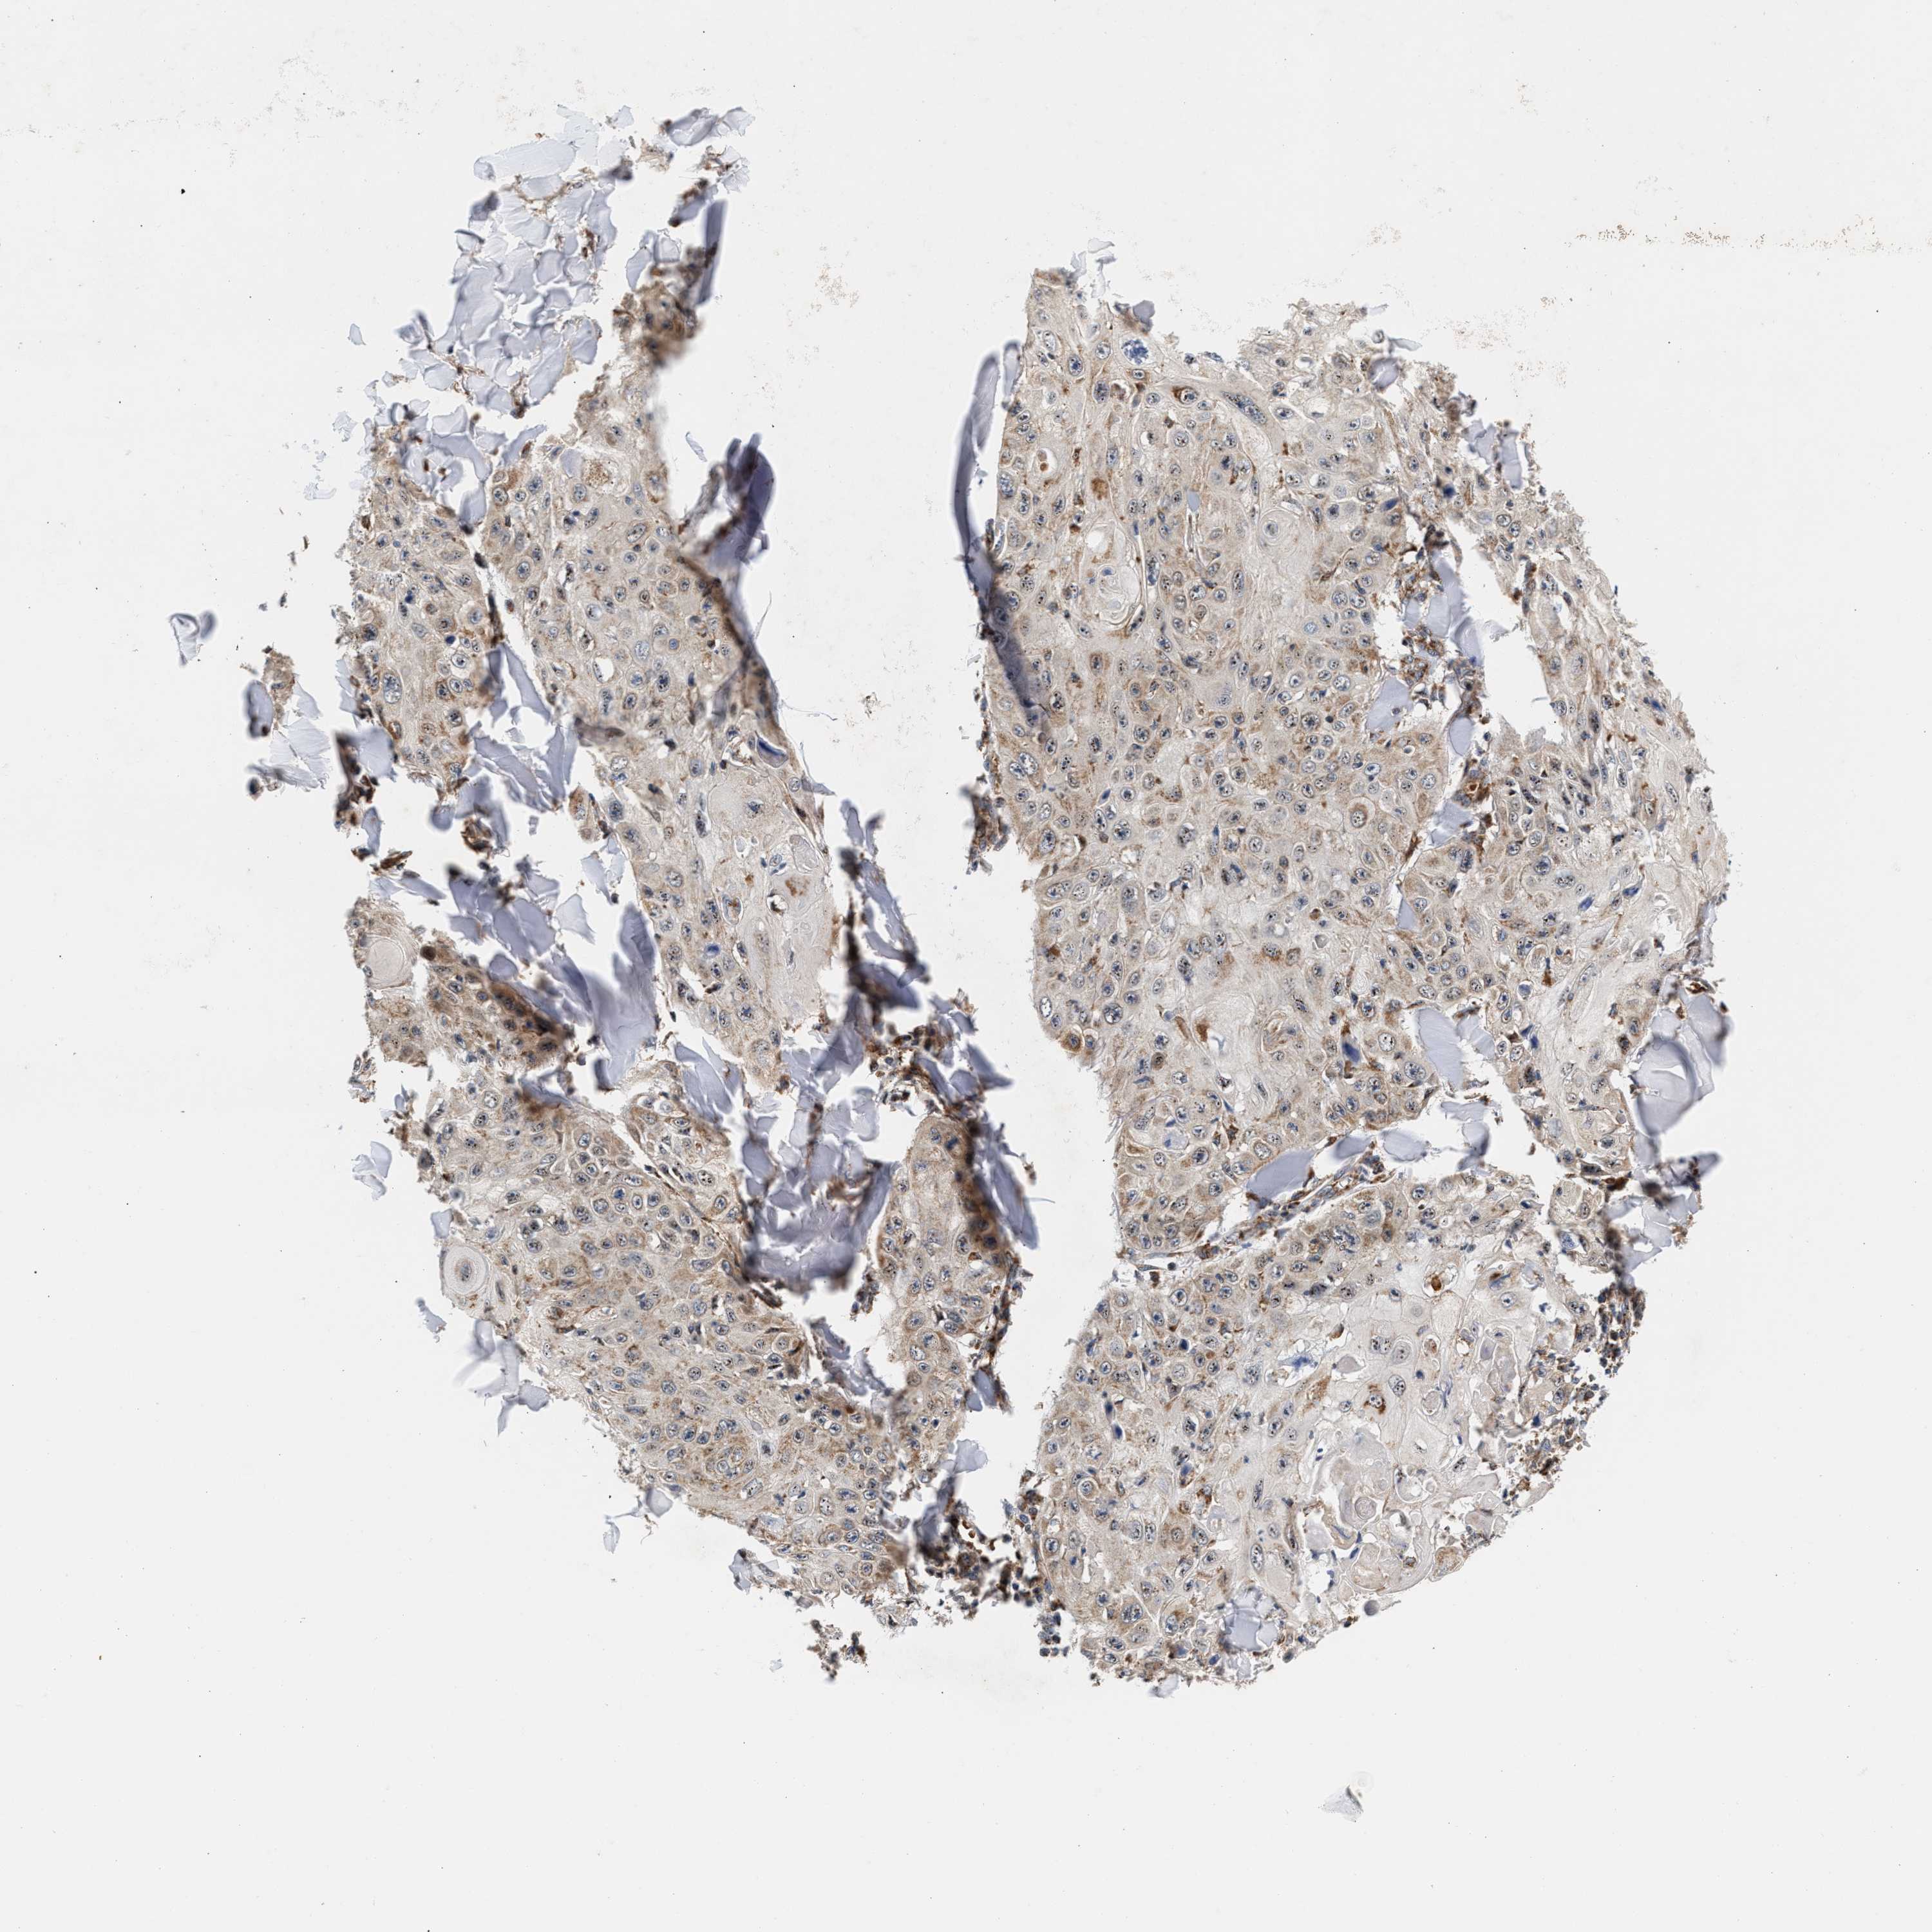

SKIN CANCER - Protein expressioni

A mouse-over function shows sample information and annotation data. Click on an image to view it in a full screen mode. Samples can be filtered based on level of antibody staining by selecting one or several of the following categories: high, medium, low and not detected. The assay and annotation is described here.

Each image is clickable and will lead to virtual microscopy that enables deeper exploration of all samples and also displays staining intensity scores, fraction scores and subcellular localization as well as patient and tissue information for each sample.

Antibody CAB025148

Staining

Low

Squamous cell carcinoma, metastatic, NOS